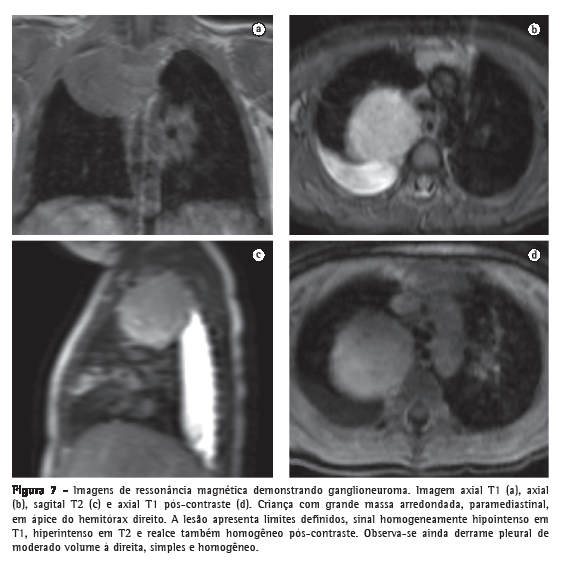

Os tumores neurogênicos são encontrados mais comumente no mediastino posterior, na região paravertebral, e muitas vezes identifica-se sua relação com o forame neural (Figura 7). As lesões podem ser originárias do nervo periférico, benignas (neurofibroma e schwannoma) ou malignas (neurofibrossarcoma), ou do gânglio simpático (ganglioneuroma, ganglioneuroblastoma e neuroblastoma). As lesões benignas são mais comumente caracterizadas como massas esféricas ou lobuladas, com alto sinal T2, reforço intenso pós-contraste e com aspecto homogêneo, com exceção do neuroblastoma, que pode ser mais heterogêneo, inclusive com calcificações. Já as lesões malignas tendem a ser maiores, mais irregulares, mais heterogêneas e com sinais de invasão da medula e da coluna torácica.(57)